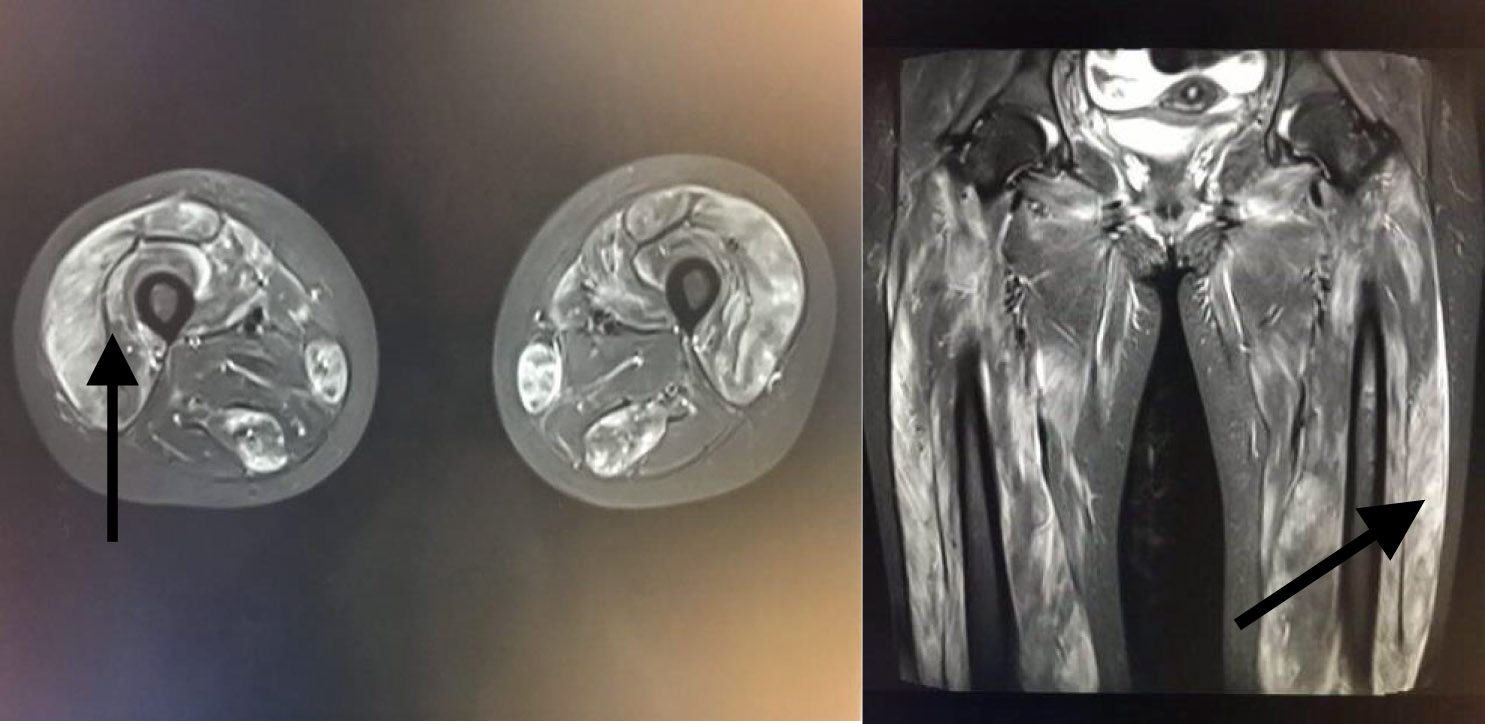

| 图 1 下肢MRI(箭头所指为肌肉水肿表现) |

患者,女,20岁,主因“四肢无力9 d,无尿7 d”入院。9 d前无明显诱因出现乏力肌痛,伴随酱油色尿、少尿,当地医院查CK、尿肌红蛋白明显升高,予水化、碱化及透析治疗CK未见明显下降转诊。既往体健,否认用药史。查体:T37.8℃,P120次/min,RR18次/min, Bp147/68 mmHg(1mmHg=0.133Kpa), 双侧大腿可见瘀斑,轻度水肿,有压痛,近端肌力4级。双肺呼吸音低,未及啰音,心律齐,腹软,无压痛。辅助检查:血生化ALT1 065 IU/L,AST3 530 IU/L Scr332.7 μmol/L, eGFR16.375 mL/(min·1.73m2), BUN15.27 μmol/L, CK>8 000 U/L,肌红蛋白>4 140 ng/mL。尿常规:蛋白质+++,红细胞150~180 /HP,WBC100~120/HP。直接抗人球蛋白实验阴性。肌炎抗体阴性。血尿免疫固定电泳未见单克隆免疫球蛋白区带。感染方面筛查:肝炎抗体、CMV/EBV-DNA、呼吸道九种病毒、布氏杆菌、莱姆病、流行性出血热抗体、军团菌皆阴性;高通量病原体检测未检出原核微生物、病毒、真核微生物。重金属筛查阴性。糖化蛋白、甲状腺功能正常。肾脏超声:双肾体积增大且实质回声增强,结构欠清晰。大腿肌肉核磁:双大腿肌肉及双侧下肢肌带肌弥漫水肿,左侧股外侧肌肌筋膜水肿(图 1)。入院诊断横纹肌溶解合并急性肾损伤。治疗上,最初间断多次行高通量血液透治疗,血肌酐下降但尿量无明显恢复,且CK水平高居不下。进一步完善的肌肉活检结果(左肱二头肌肌肉)提示:肌纤维坏死、再生,伴随肌束血管周围少量炎细胞浸润,许多肌间毛细血管NSE深染,符合坏死性肌病样病理改变特点(图 2)。根据肌肉活检结果考虑免疫介导性坏死性肌病,行激素治疗(甲泼尼龙40 mg/d静点连续10 d后调整为口服泼尼松50 mg口服, 静脉激素治疗第3天时曾行甲泼尼龙500 mg静脉冲击1次)及2次血浆置换(每次分别置换3 000 mL)后CK明显下降,尿量也逐渐增多(图 3~4)。出院时患者口服强的松45 mg/d,尿量恢复至3 500 mL/d,生化结果:ALT67 U/L,AST26 U/L,Scr99.4 μmol/L, CK78U/L, 肌红蛋白23.5 ng/mL,尿肌红蛋白4.6 ng/mL。患者出院1个月后门诊复诊,血肌酐和ck正常,尿量正常,转归良好。

NAM患者肌酶升高以CK为主,一般高于正常值10倍以上,发病初期可达数万。可同时伴有ALT、AST、LDH升高,一些NAM患者血清中肌炎抗体如抗SRP抗体、抗HMGCR抗体、肌炎特异性抗体(myositis specific autoantibody,MSA)可阳性表达。在MRI上,MNM可表现为STIR序列高信号,这提示组织水肿,臀大肌和股四头肌后方肌群受累易见。肌肉病理上,HE染色中,NAM的显著特点是大量肌纤维坏死,可见再生肌纤维。免疫组织化学染色可见肌纤维膜MAC和MHC-I阳性。本例患者为年轻女性,急性起病,双下肢近端肌痛、力弱,CK升高10倍以上,伴随肝酶升高,肌炎抗体阴性,肌肉核磁显示肌肉水肿,肌肉病理提示免疫介导的坏死性肌病,符合上述NAM诊断标准。糖皮质激素是治疗NAM的一线药物,对于病情严重或者初始治疗不佳患者,可给予静注激素。激素效果不佳可应用免疫抑制剂或者静脉应用丙种球蛋白。本例患者确诊NAM后,给予激素和丙种球蛋白治疗,血浆置换辅助治疗后CK、肝酶很快明显下降至正常,临床改善,转归良好。临床上,对经充分水化、特别肾脏替代治疗后CK仍高居不下的横纹肌溶解需考虑有炎性肌肉病可能。可区分MNM患者与横纹肌溶解患者的特征包括:症状和表现(包括CK升高)在不进行免疫抑制治疗时持续存在,进一步完善肌肉影像学检查和肌肉活检明确患者的组织病理学变化。尽早明确诊断、给予免疫调节治疗,可免漏诊误诊、减少患者痛苦。